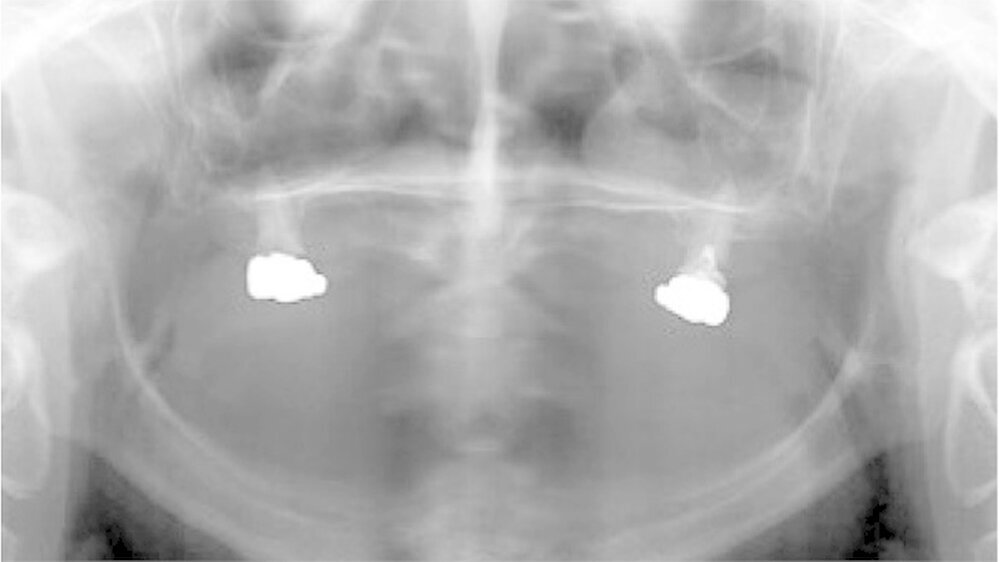

Der bei Behandlungsbeginn 14-jährige Patient war mit einer neun beziehungsweise fünfjährigen Prothese im Unter- beziehungsweise Oberkiefer versorgt (Abb. 2 und 3). Die angelegten Zapfenzähne 12, 11 und 21 waren bereits mehrfach konservierend restauriert und wiesen diverse Stellen mit Sekundärkaries auf. Die Kronenränder der Zähne 33 und 43 waren deutlich sondierbar. Der Kieferkamm im Unterkiefer war aufgrund der fehlenden Zahnanlagen sehr schmal (Abb. 4 bis 6). Die Panoramaschichtaufnahme zeigte das reduzierte vertikale Knochenangebot (Abb. 7). Da die Vitalerhaltung der wenigen Restzähne aufgrund des jungen Alters des Patienten unbedingt anzustreben war, wurde als Behandlungsziel im Ober- und Unterkiefer eine Versorgung mit Hybridprothesen, retiniert auf Teleskopkronen, festgelegt.

Bei dieser bei Behandlungsbeginn 16-jährigen Patientin waren seit Geburt nur die beiden ersten Molaren im Oberkiefer ausgebildet. Die Folge waren schmale und niedrige Alveolarkämme mit einem flachen Gaumengewölbe (Abb. 16 und 17). Die röntgenologische Abbildung bestätigte das geringe vertikale Knochenangebot. Eine Formanomalie der Zahnwurzeln ließ auf taurodonte Molaren schließen. Beide Molaren wiesen ausgedehnte kariöse Läsionen auf (Abb. 18).